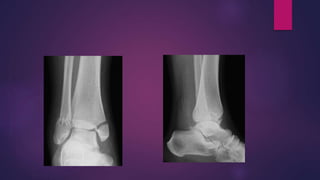

SUPINATION EXTERNAL ROTATION

SUPINATION ADDUCTION